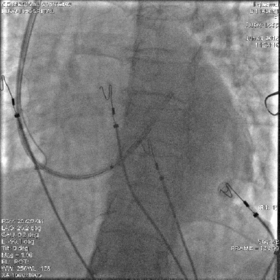

CRT-D植入过程

冠状窦十极进入冠状窦口,遇阻力无法前行

反复调整角度后长鞘进入冠状窦口

鞘管位置较低且向远端推送有阻力,考虑可能超选进入后静脉,需造影确定鞘管位置

经长鞘直接造影确定鞘管位置

造影示鞘管已经超选进入后静脉,不在冠状窦主干内,同时侧静脉及冠状静脉主干显影。可见冠状静脉主干向上,走形角度较大

“双泥鳅”法进入冠状窦主干

将一根泥鳅留在后静脉内作为支撑,回撤长鞘至冠状窦口,使用另一根泥鳅按造影显示进入冠状窦主干

将长鞘送入冠状窦主干

顺利找到冠状窦主干,将两根泥鳅都送入主干内加强支撑,再送入长鞘